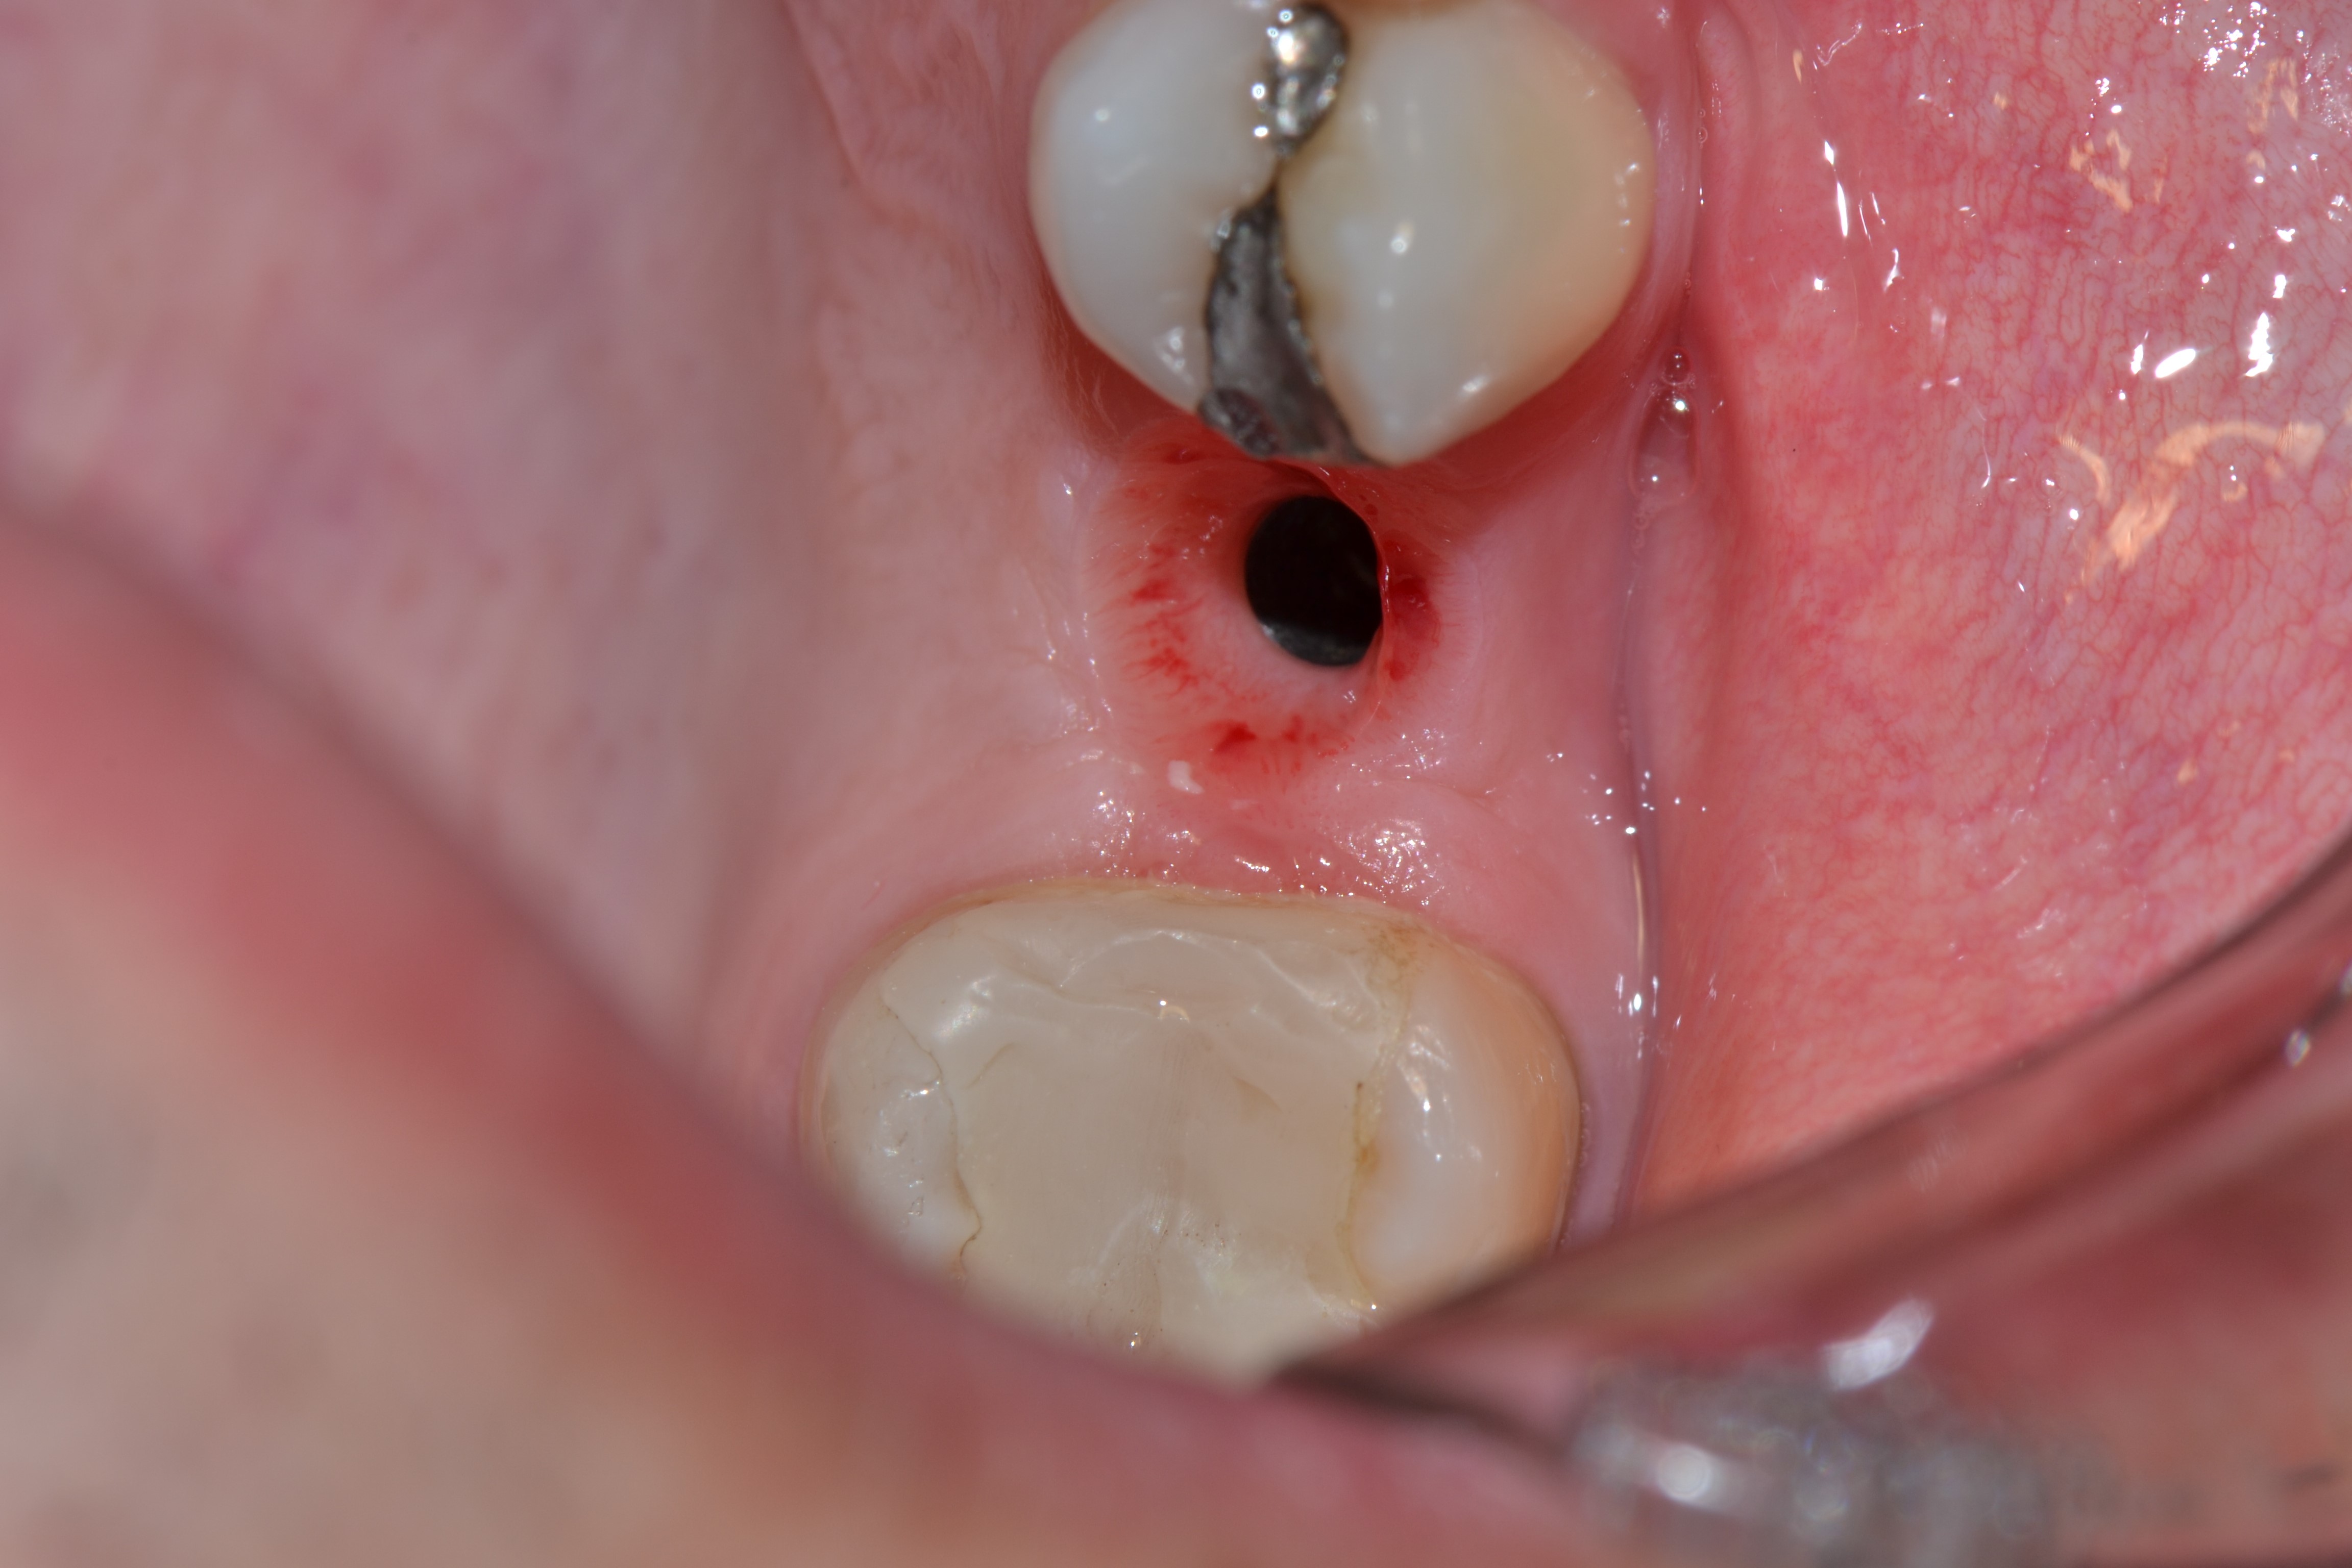

Em anamnese, nenhum desvio de base foi relatado. Em exame clínico e radiográfico foi constatada raiz residual do elemento 24 (Figura 1). O paciente foi pré-medicado com 2g de Amoxicilina e 4mg de Dexametasona, 1 hora antes do procedimento cirúrgico.

Figura 1: Radiografia Inicial